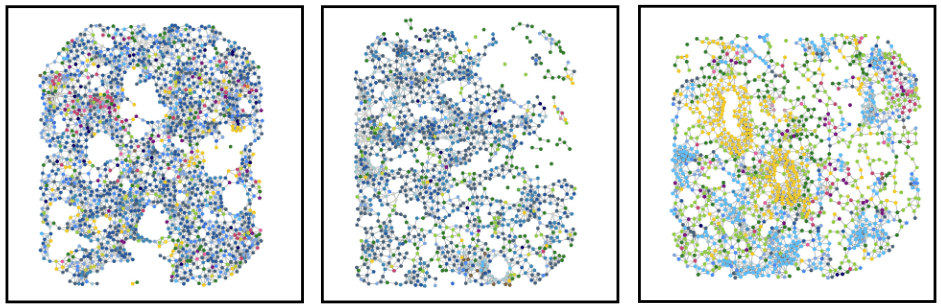

Bi-level graph learning for breast cancer biomarkers

Undirected graph: \(G = (V,W)\)

Set of nodes \(v_i = (v^\text{loc}_i,x^\text{type}_i)\)

Set of edges \(W \subseteq \{(v_i,v_j)| v_i\neq v_j\} \)

cell phenotype \(x_i^\text{type} \in \{1,\dots,K\}\)

\(w_{i,j} = \exp(-\alpha \|v^\text{loc}_i-v^\text{loc}_j\|^2_2) \)

coordinates \(v_i^\text{loc} \in\mathbb R^2\)

Graph Kernels

generate

subtrees

\(\kappa(G_1,G_2) = \frac{\langle \phi(G_1), \phi(G_2) \rangle}{\|\phi(G_1)\|_2\|\phi(G_2\|_2}\)

\(=0.301\)

Soft WL-kernel:

[Shervashidze, et al JMLR (2011)][Schulz et al. ML (2022)]

Bi-level Graphs: BiGraph

Community detection via

Louvain algorithm [Biondel et al, 2008]